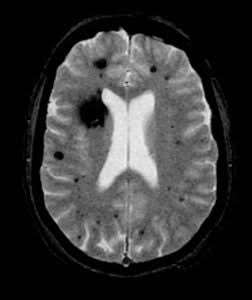

Cavernous malformations are usually detected through an MRI scan, which provides detailed images of the brain and can reveal the size, location, and characteristics of the lesion. Special MRI sequences such as susceptibility-weighted imaging (SWI) and gradient echo improve the ability to detect even small cavernous malformations or multiple lesions.

Individuals with the familial (genetic) form of cavernous malformations are likely to have multiple lesions and may be more likely to experience symptoms associated with the disorder.